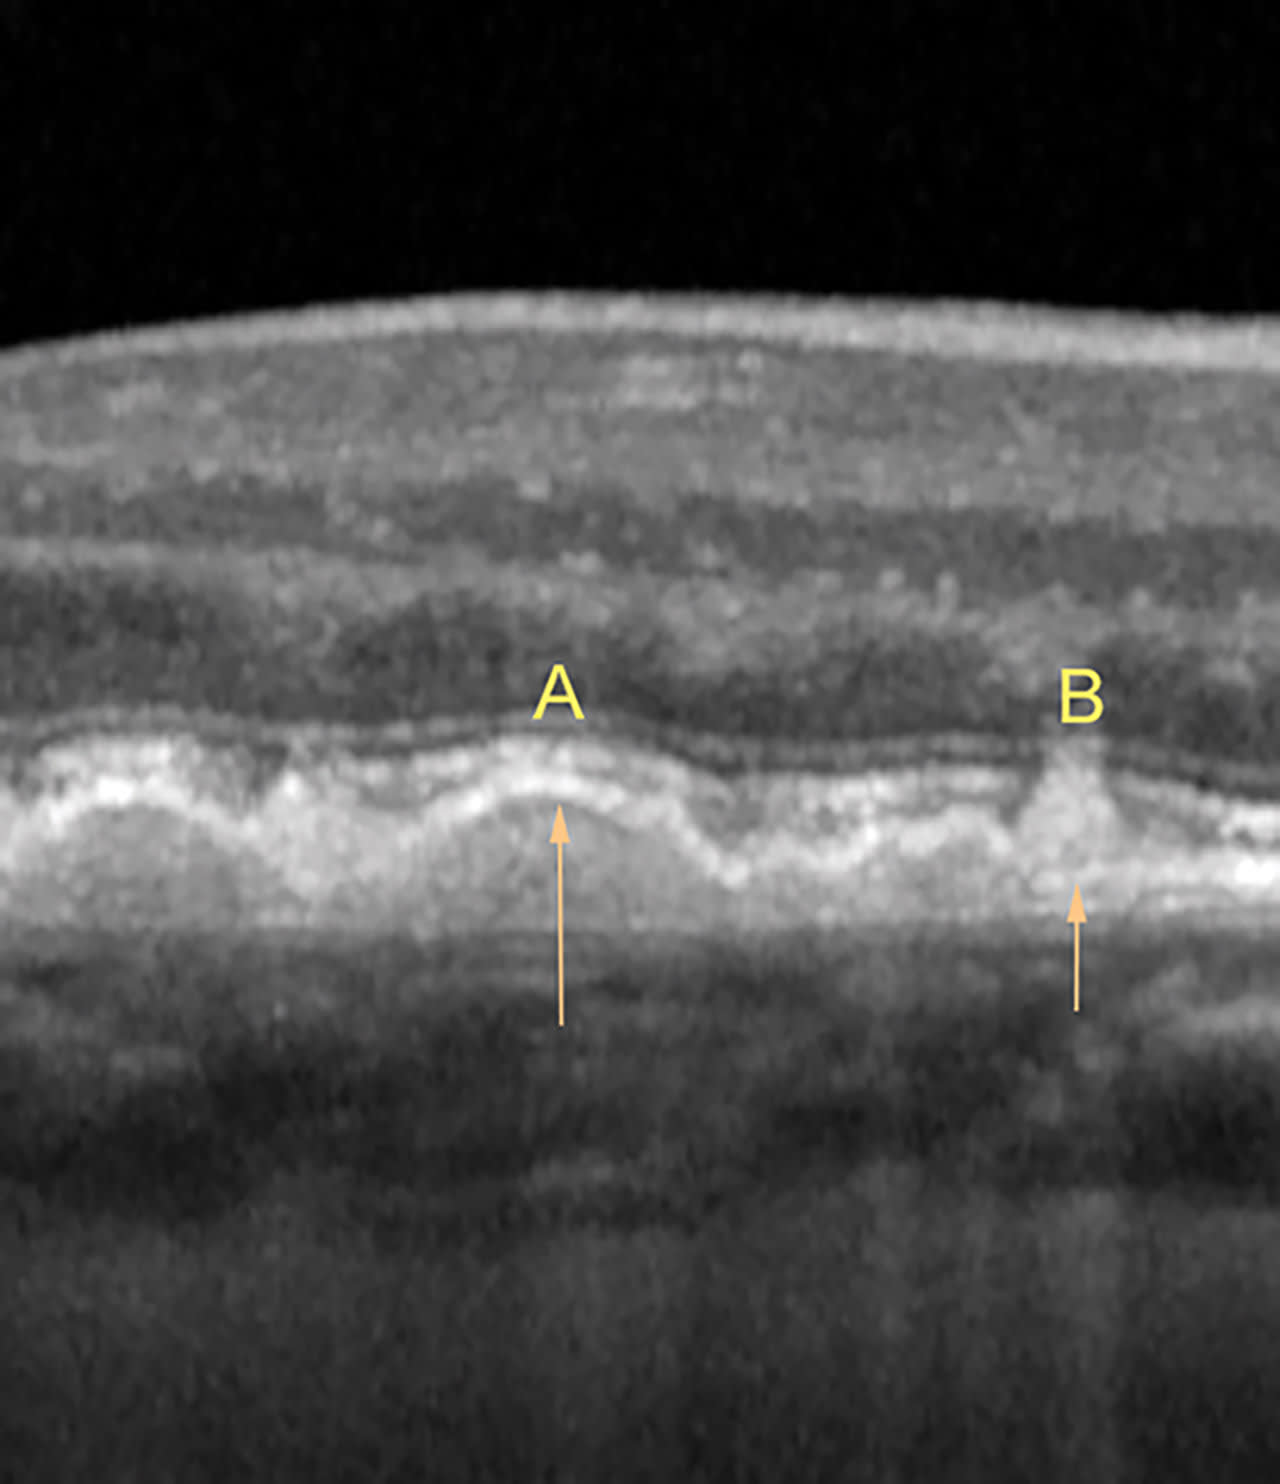

Soft drusen develop under the RPE and have a round, dome appearance. (Figure 8a). Hard drusen are also sub-RPE but have a conical or peaked appearance (Figure 8b). Reticular pseudodrusen are present above the RPE (Figure 9) and can provide further prognostic value, as patients with RPD have a significant risk for the progression of age-related macular degeneration (AMD).3